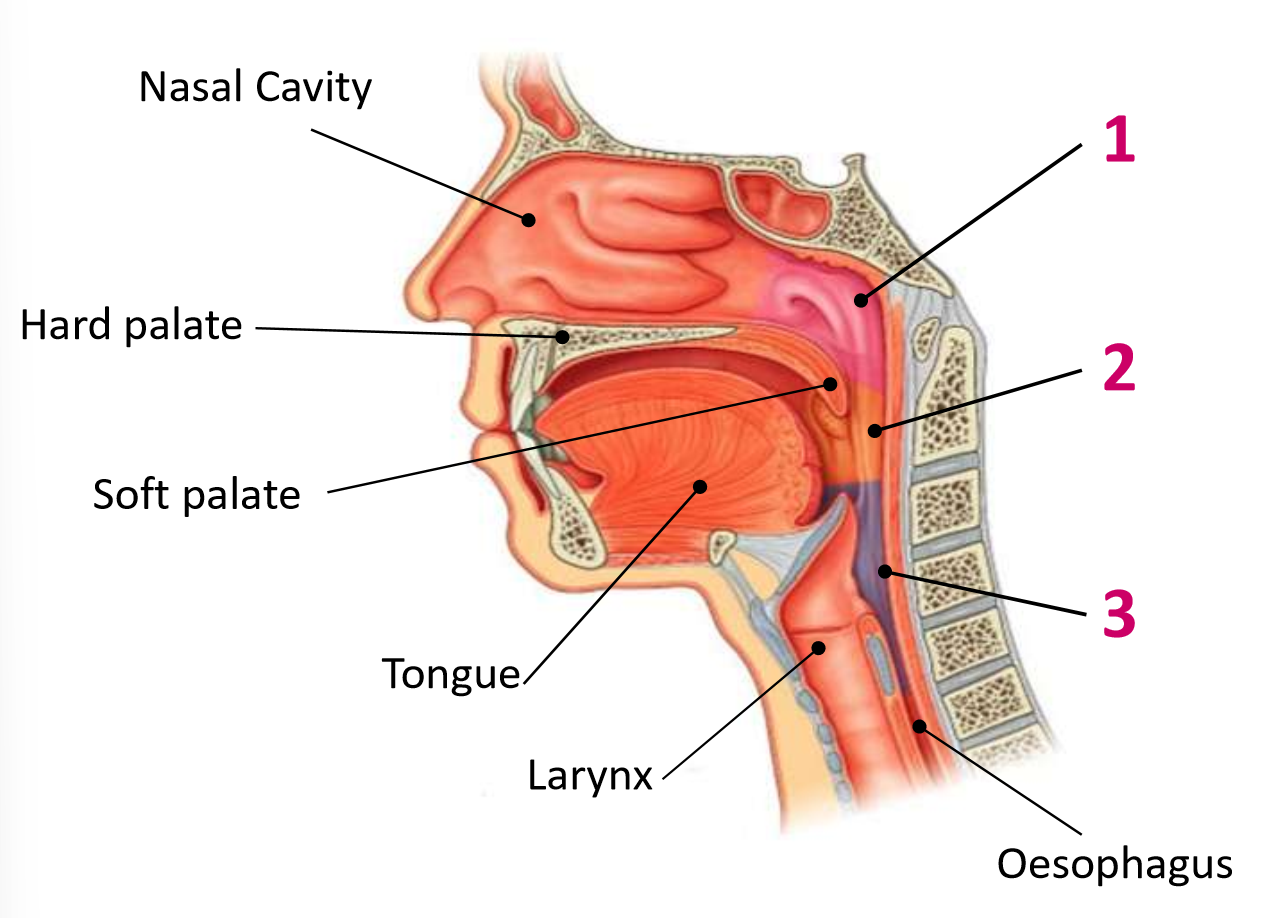

Which area of the head and neck do 1, 2, and 3 make?

pharynx

What region is 1?

nasopharynx

What region is 2?

oropharynx

What region is 3?

laryngopharynx

What is the anterior wall of 1?

posterior nasal choanae

What is the roof of 1?

body of sphenoid and basilar part of occipital

What is the posterior wall of 1?

anterior arch of atlas covered in pharyngobasilar fascia

What is the floor of 1?

soft palate

What is the anterior wall of 2?

oropharyngeal isthmus

What is the roof of 2?

soft palate

What is the floor of 2?

pharyngeal part of tongue and glossoepiglottic fold

What is the posterior wall of 2?

C2 and upper C3

What are the lateral walls of 2?

palatoglossal and palatopharyngeal arches